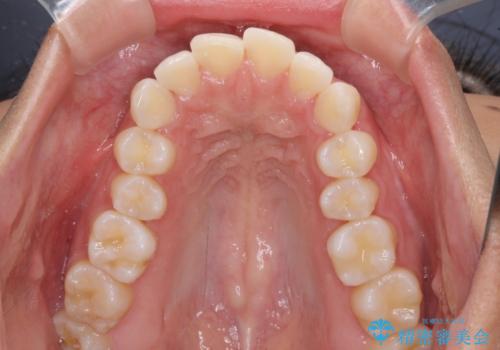

- 下唇が突き出るような口元の突出感が気になるとのことで来院された患者様です。

上下顎ともに前突した歯列であったので、上下ともに左右の第1小臼歯4本を抜歯し、ワイヤー装置にて矯正治療を行うこととしました。

抜歯スペースに前歯を移動させることで歯の突出感が改善され、非常に唇が閉じやすい仕上がりとなりました。